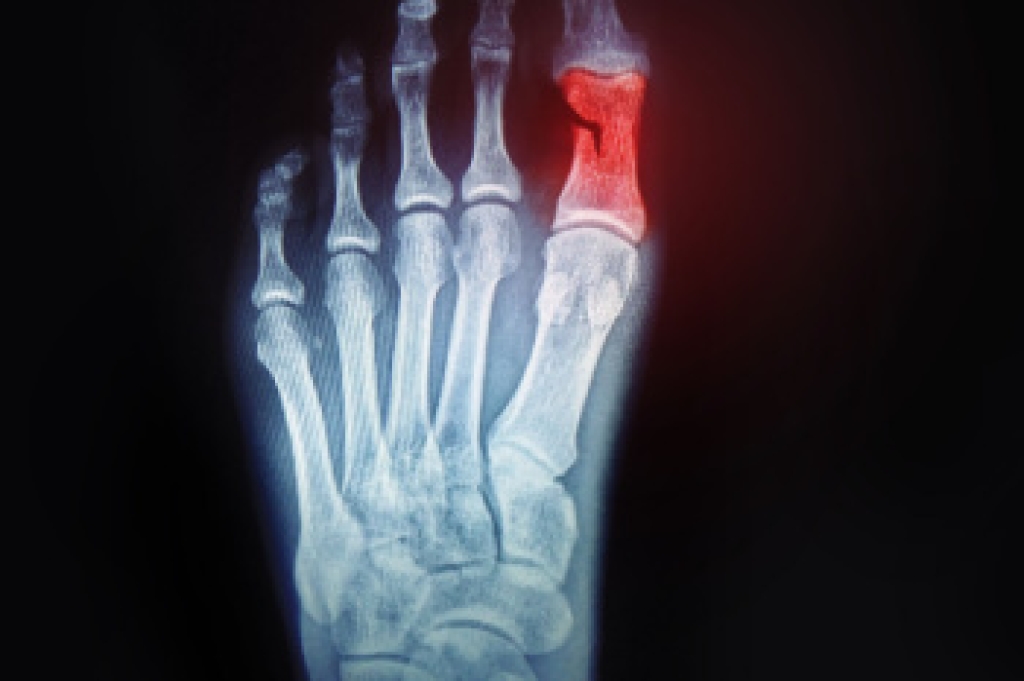

To properly diagnose the exact type of injury, podiatrists will conduct a number of different tests. Some of these include sensation and visual tests, X-rays, and MRIs. Medical and family histories will also be taken into account.

Once the injury has been diagnosed, the podiatrist can than offer the best treatment options for you. In less severe cases, rest and keeping pressure off the foot may be all that’s necessary. Orthotics, such as a specially made shoes, or immobilization devices, like splints or casts, may be deemed necessary. Finally, if the injury is severe enough, surgery may be necessary.